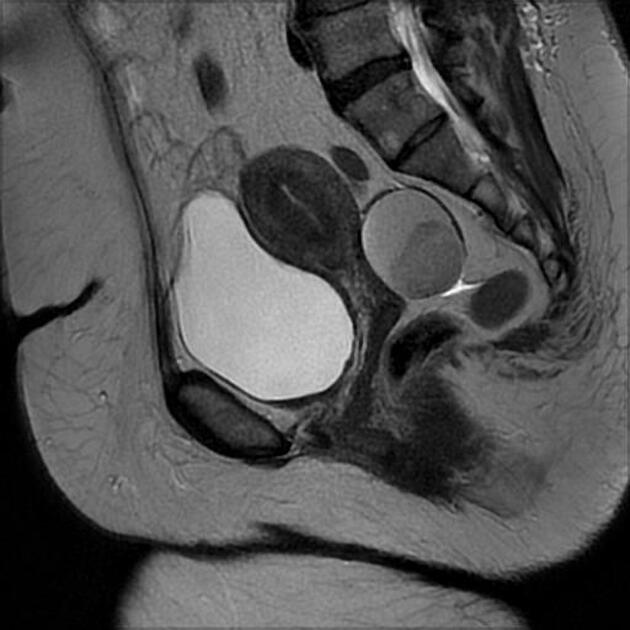

Признаки эндометриоидной кисты яичника на МРТ

Эндометриоидная киста яичника на томограммах может проявляться следующими признаками:

- Наличие чётко очерченного образования округлой или овальной формы в ткани яичника, которое отграничено от окружающих тканей и имеет плотную стенку, что указывает на длительное существование кисты.

- Утолщение стенки кисты, что связано с хроническим воспалительным процессом, сопровождающим эндометриоз, и может проявляться в виде неровных или утолщённых участков в структуре стенки кисты.

- Деформация структуры яичника в области расположения кисты, что приводит к изменению анатомической формы яичника и нарушению его нормальной функциональной структуры.

- Прилегание кисты к другим органам малого таза, таким как матка или фаллопиевы трубы, что может вызывать сдавление или смещение окружающих тканей, особенно при увеличении размеров кисты.

- Наличие спаек между кистой и прилегающими структурами, что является характерным для эндометриоидных кист и приводит к нарушению нормальной анатомической подвижности органов малого таза.

Как выглядит эндометриоидная киста яичника на сканах МРТ

На Т1-взвешенных изображениях киста демонстрирует гиперинтенсивный сигнал, что указывает на наличие густого содержимого, характерного для эндометриоидной кисты, наполненной старой кровью.

На Т2-взвешенных изображениях киста проявляется как зона с пониженным сигналом, что связано с высоким содержанием железа и продуктов распада гемоглобина, характерных для старых кровоизлияний внутри кисты.

На томограммах с подавлением жира эндометриоидная киста хорошо выделяется на фоне жировой клетчатки, что позволяет чётко визуализировать её границы и дифференцировать от других кистозных образований.

МРТ с контрастом могут демонстрировать отсутствие значительного усиления сигнала от содержимого кисты, что указывает на отсутствие активного кровоснабжения внутри кисты и помогает отличить её от других типов опухолевых образований.